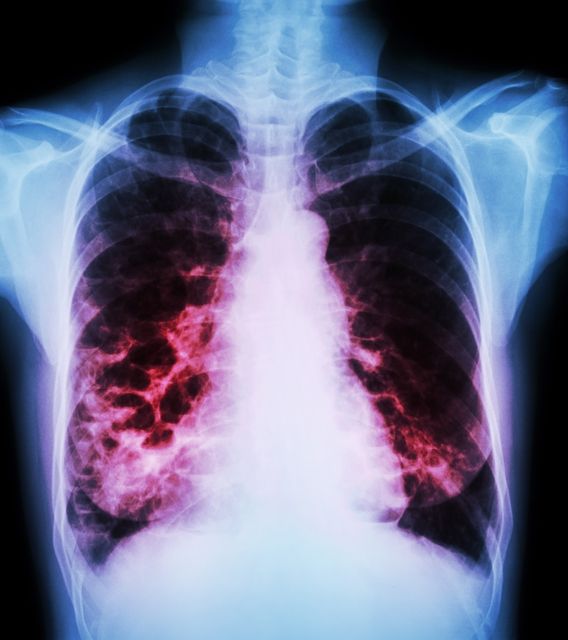

Αναπνευστικές Παθήσεις

1. Χρόνια Αποφρακτική Πνευμονοπάθεια (ΧΑΠ)

3. Λοιμώξεις Αναπνευστικού

4. Ιδιοπαθής Πνευμονική ίνωση και διάμεσες πνευμονοπάθειες

11. Επαγγελματικές παθήσεις των πνευμόνων

12. Αγγειακές παθήσεις των πνευμόνων και Πνευμονική Υπέρταση